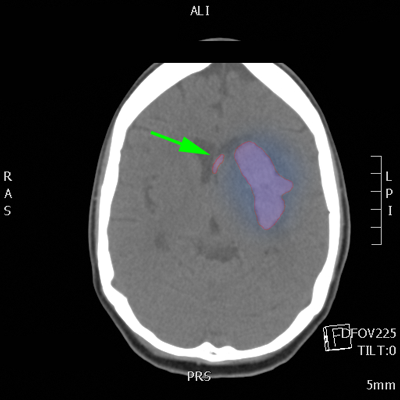

Αυτόματο ενδοεγκεφαλικό αιμάτωμα (κόκκινο περίγραμμα) με περιεστικό οίδημα (μπλέ). Αιμορραγία και στην αριστερή πλάγια κοιλία του εγκεφάλου (πράσινο βέλος). |